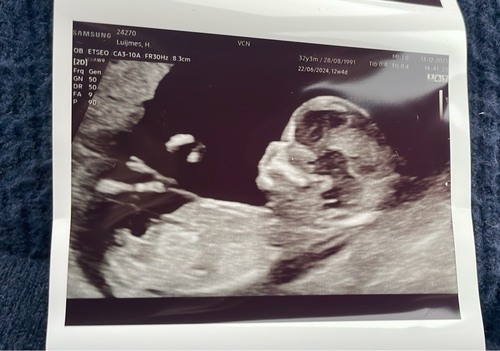

Kindje van mijn beste vriendin 🥰. 12+5 op deze foto. Kunnen jullie hier wat van maken? Ik denk zelf een meisje te zien, maar ik ben geen echte kenner!

Ik zie geen nub hierop